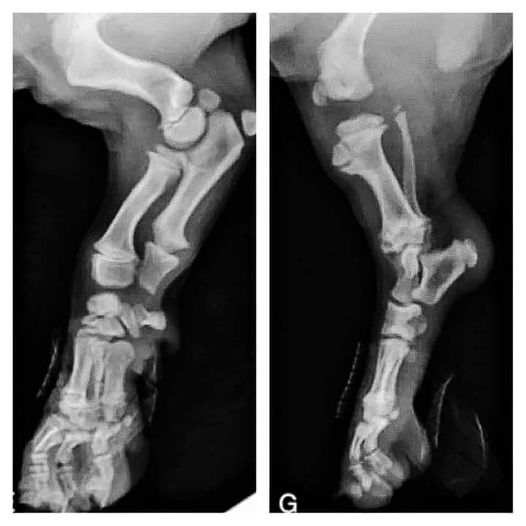

Structure – The English retriever has a bit stockier build, a blockier head, and is built a little lower to the ground.